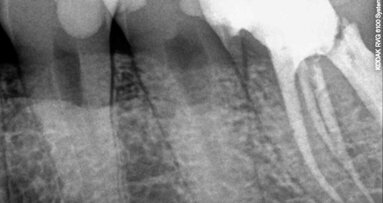

When it comes to dental care, the more doctors can see their patients’ anatomy, the more efficient they can be in their diagnosis and treatment planning. ...